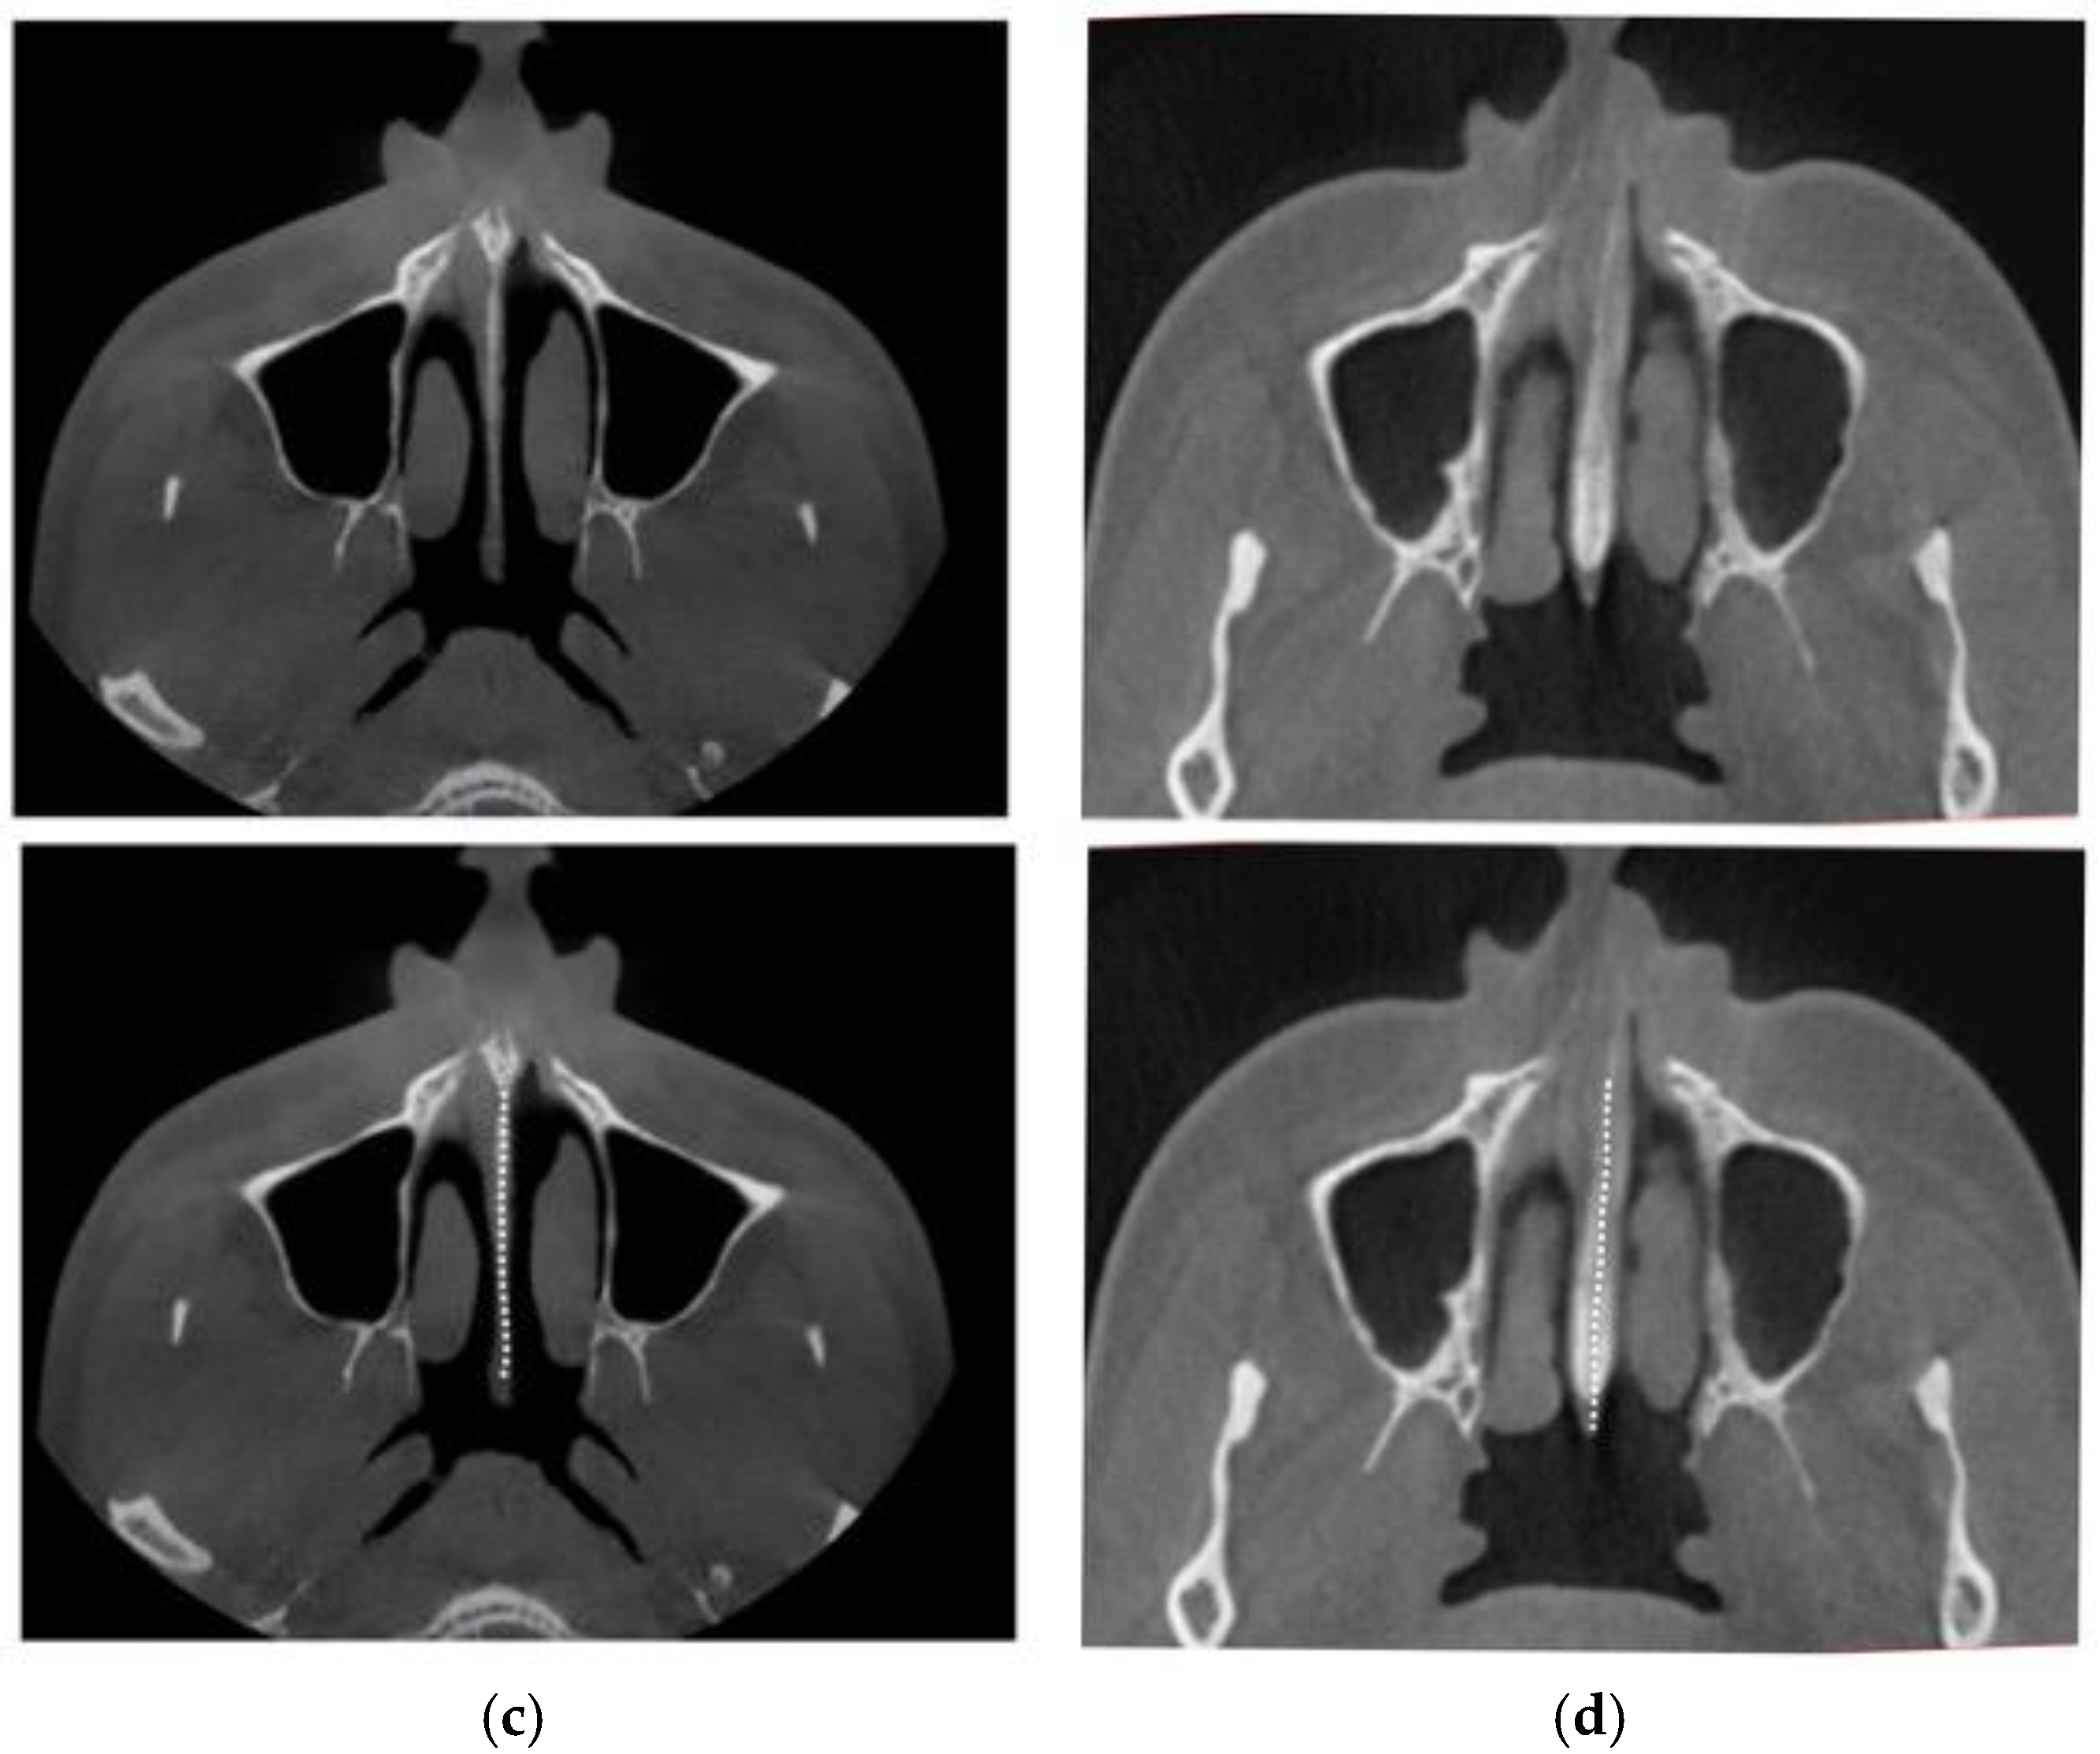

2.4. Case A: Blind Midpalatal Piezocorticotomy with MARPE Expansion

2.5. Case B: Guide-Assisted Midpalatal Piezocorticotomy